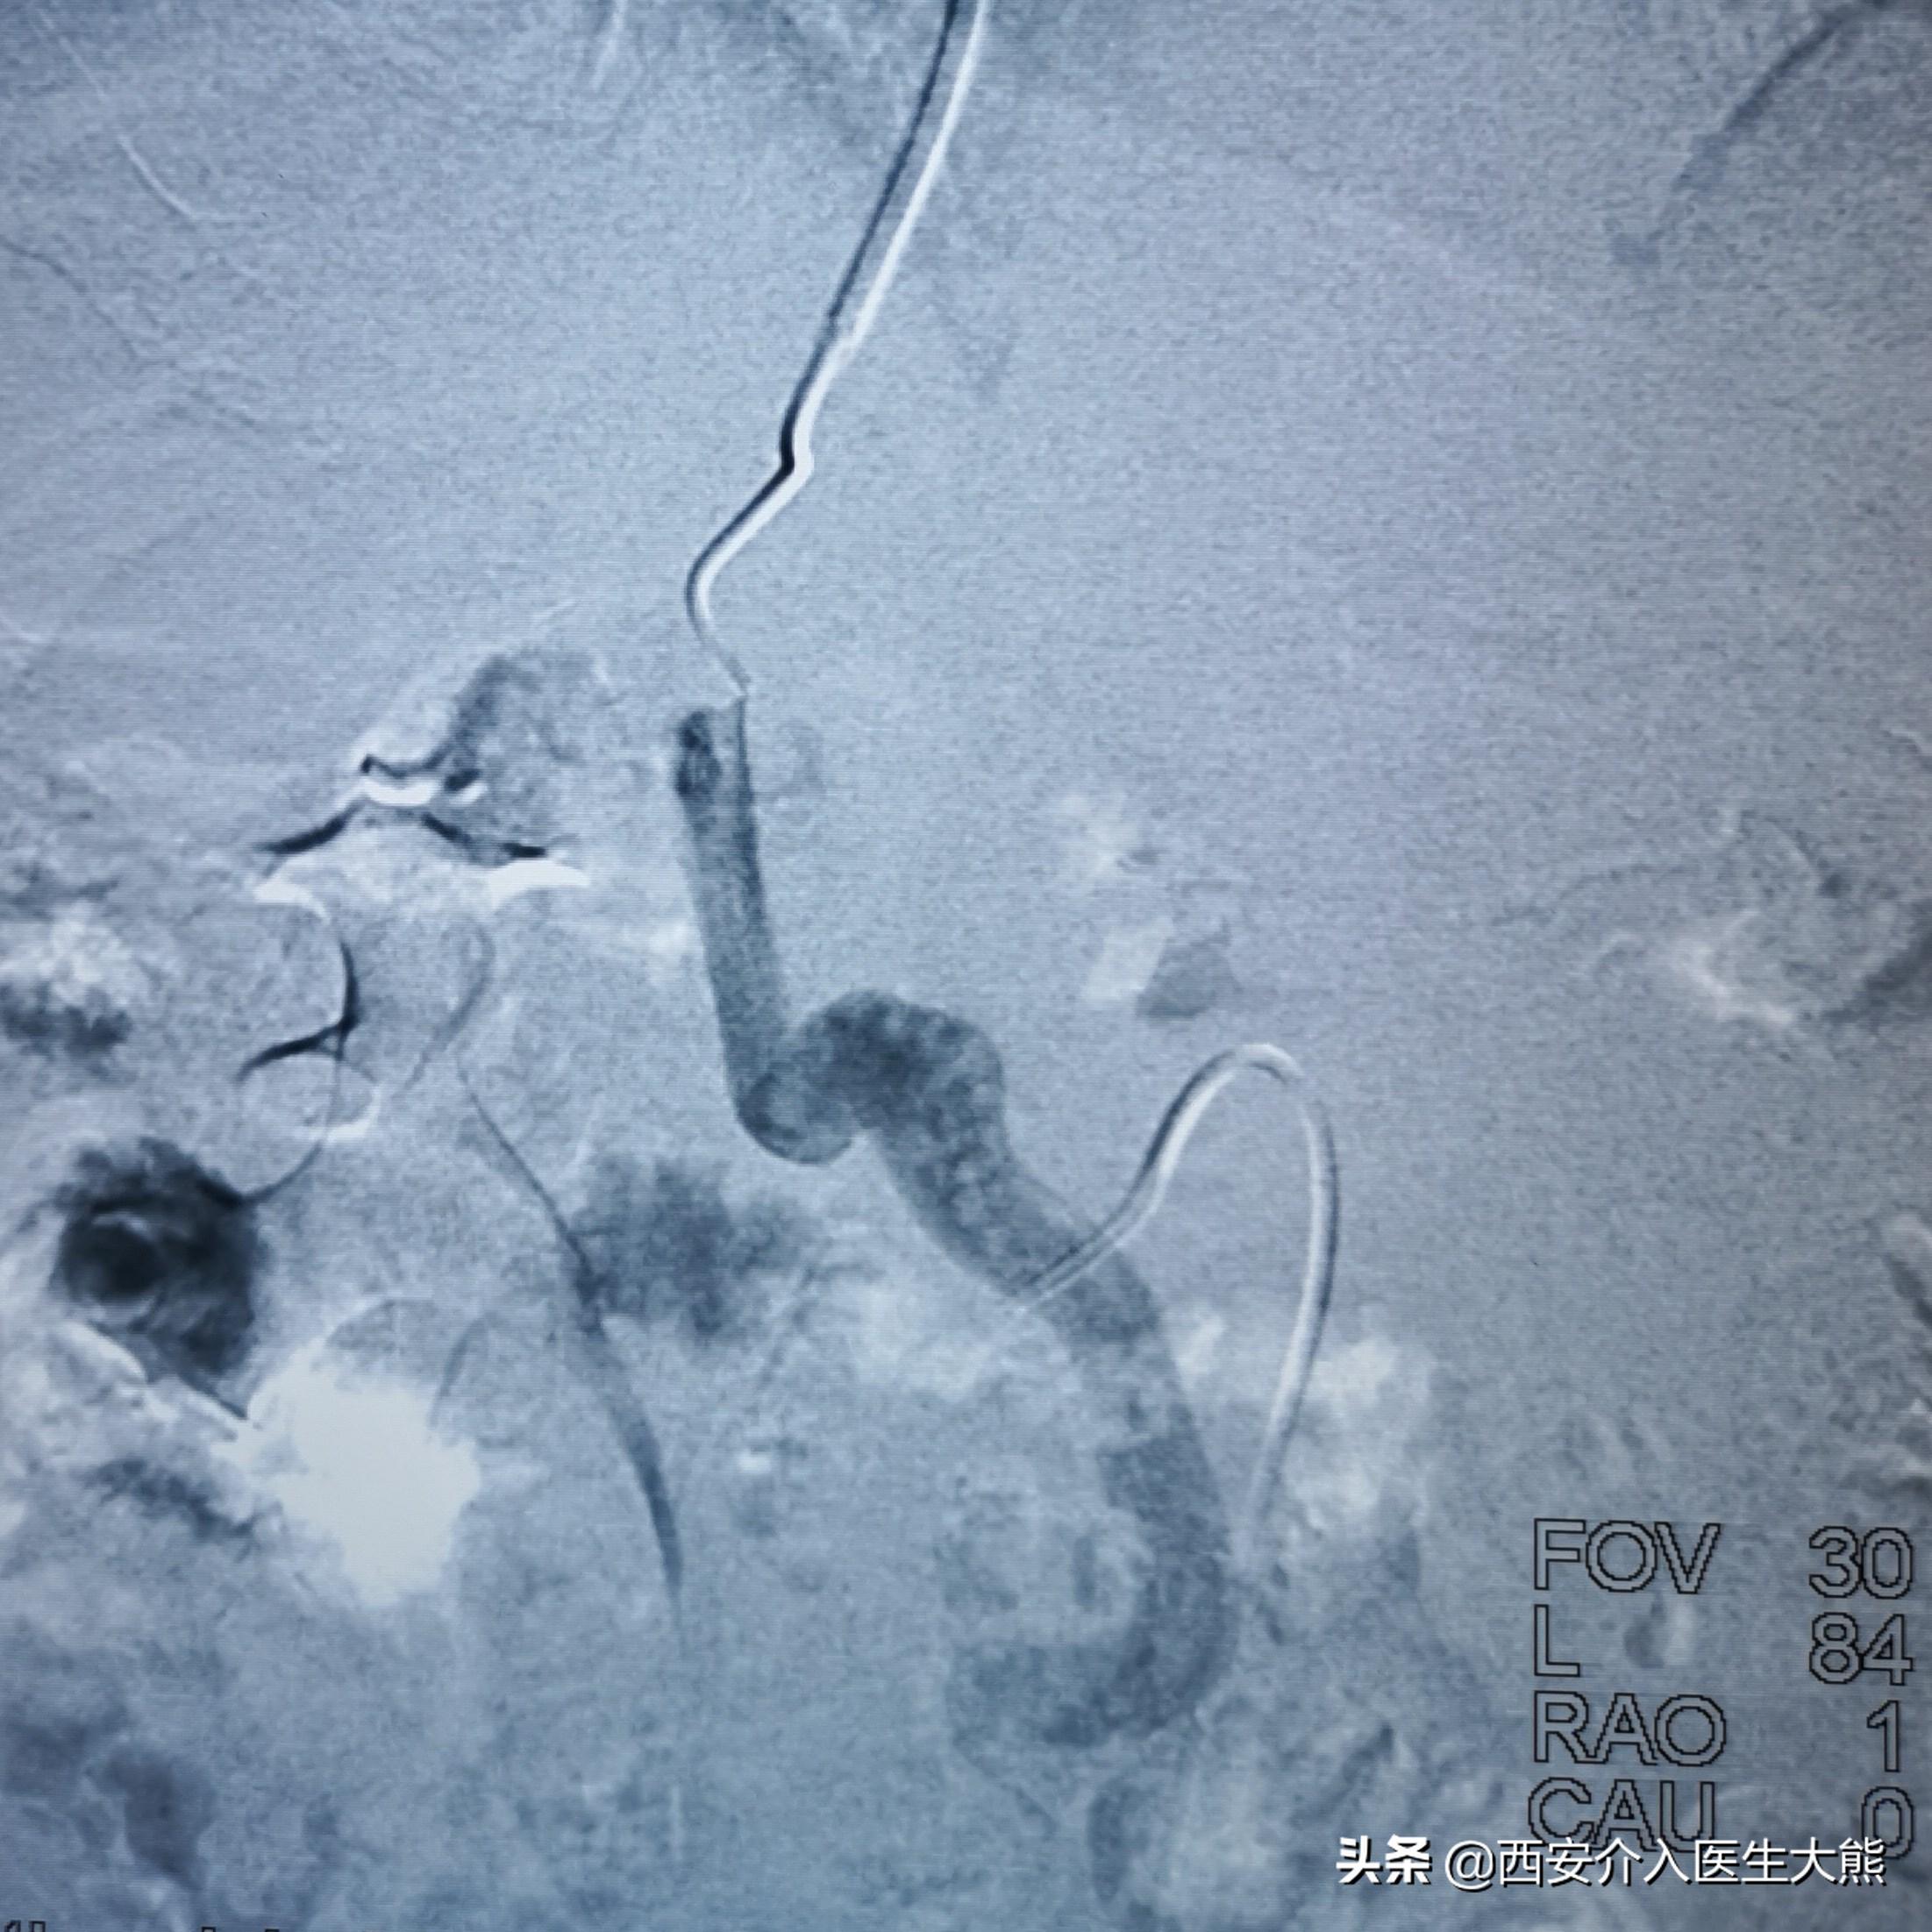

3.术中DSA:

扩张的没静脉和胃冠状静脉

扩张的胃冠状静脉

这名患者的治疗过程就符合该治疗策略。术前的CT平扫已经显示极度扩张的胃冠状静脉,这在DSA影像上得到证实。2018年患者第二次出血时做的增强CT上已经显示出患者的胃冠状静脉扩张。此时,已经具有行TIPS的指征。在经过3年的变化后,病情是急剧加重。如果出血剧烈、生命体征不平稳,或各种原因导致不能行急诊胃镜的情况下,不要错过TIPS降低门脉压力的机会。